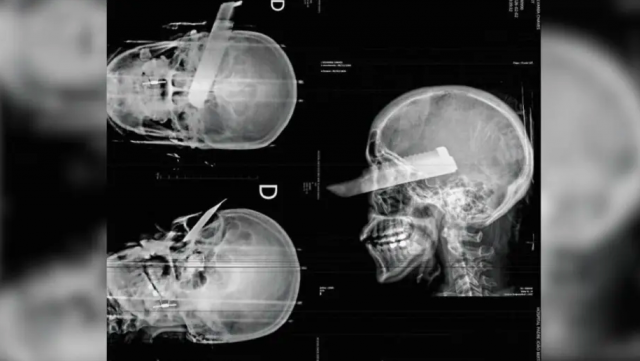

Uma mulher sofreu uma tentativa de feminicídio na manhã desta segunda-feira (2) em São Carlos, no Oeste de Santa Catarina, ao ser atacada pelo companheiro dentro da residência do casal. O agressor desferiu um golpe de faca no rosto da vítima, atingindo o olho direito, mas o crime não se consumou, segundo a polícia, graças ao pronto atendimento médico.

Conforme apurado pela Polícia Civil, o suspeito agiu com a intenção de a matar. A vítima conseguiu escapar parcialmente da agressão, mas foi atingida enquanto tentava fugir. Ela recebeu atendimento de emergência e passa por acompanhamento médico.